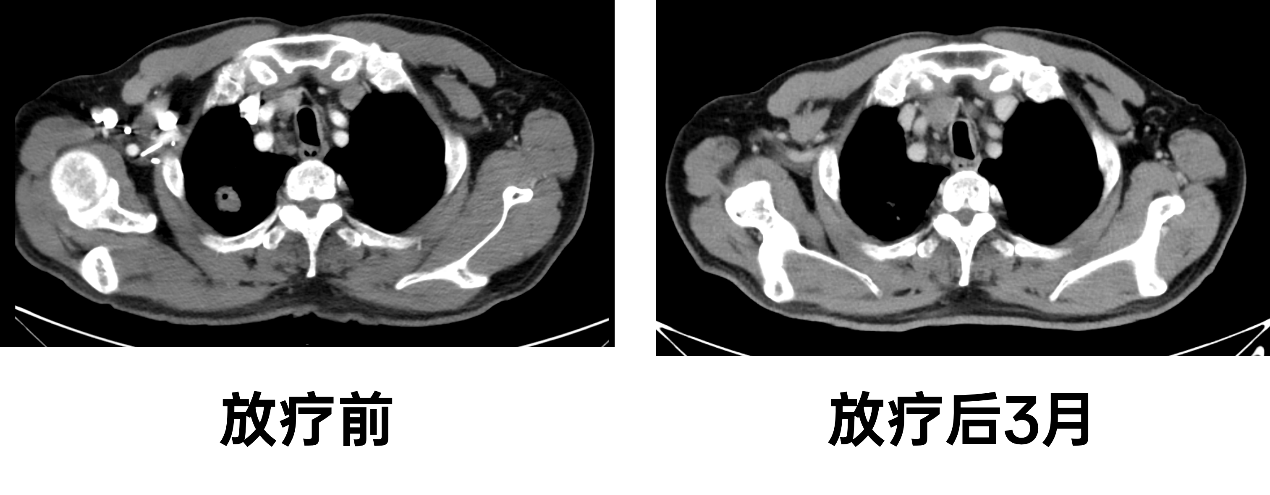

疗效评估:2024-01-04我院PET/CT复查疗效评价部分缓解。

2024-02-19 复查显示:胸部与2023-10-17日片对比:右肺上叶尖段软组织影较前范围缩小,纵隔多发肿大淋巴结较前缩小,考虑转移瘤;新增右肺下叶背段高密度影,考虑炎症;右肺中叶内侧段、右肺下叶背段实性结节较前未见明显变化,建议随诊复査;右肺下叶背侧胸膜下少许渗出性改变较前基本吸收。